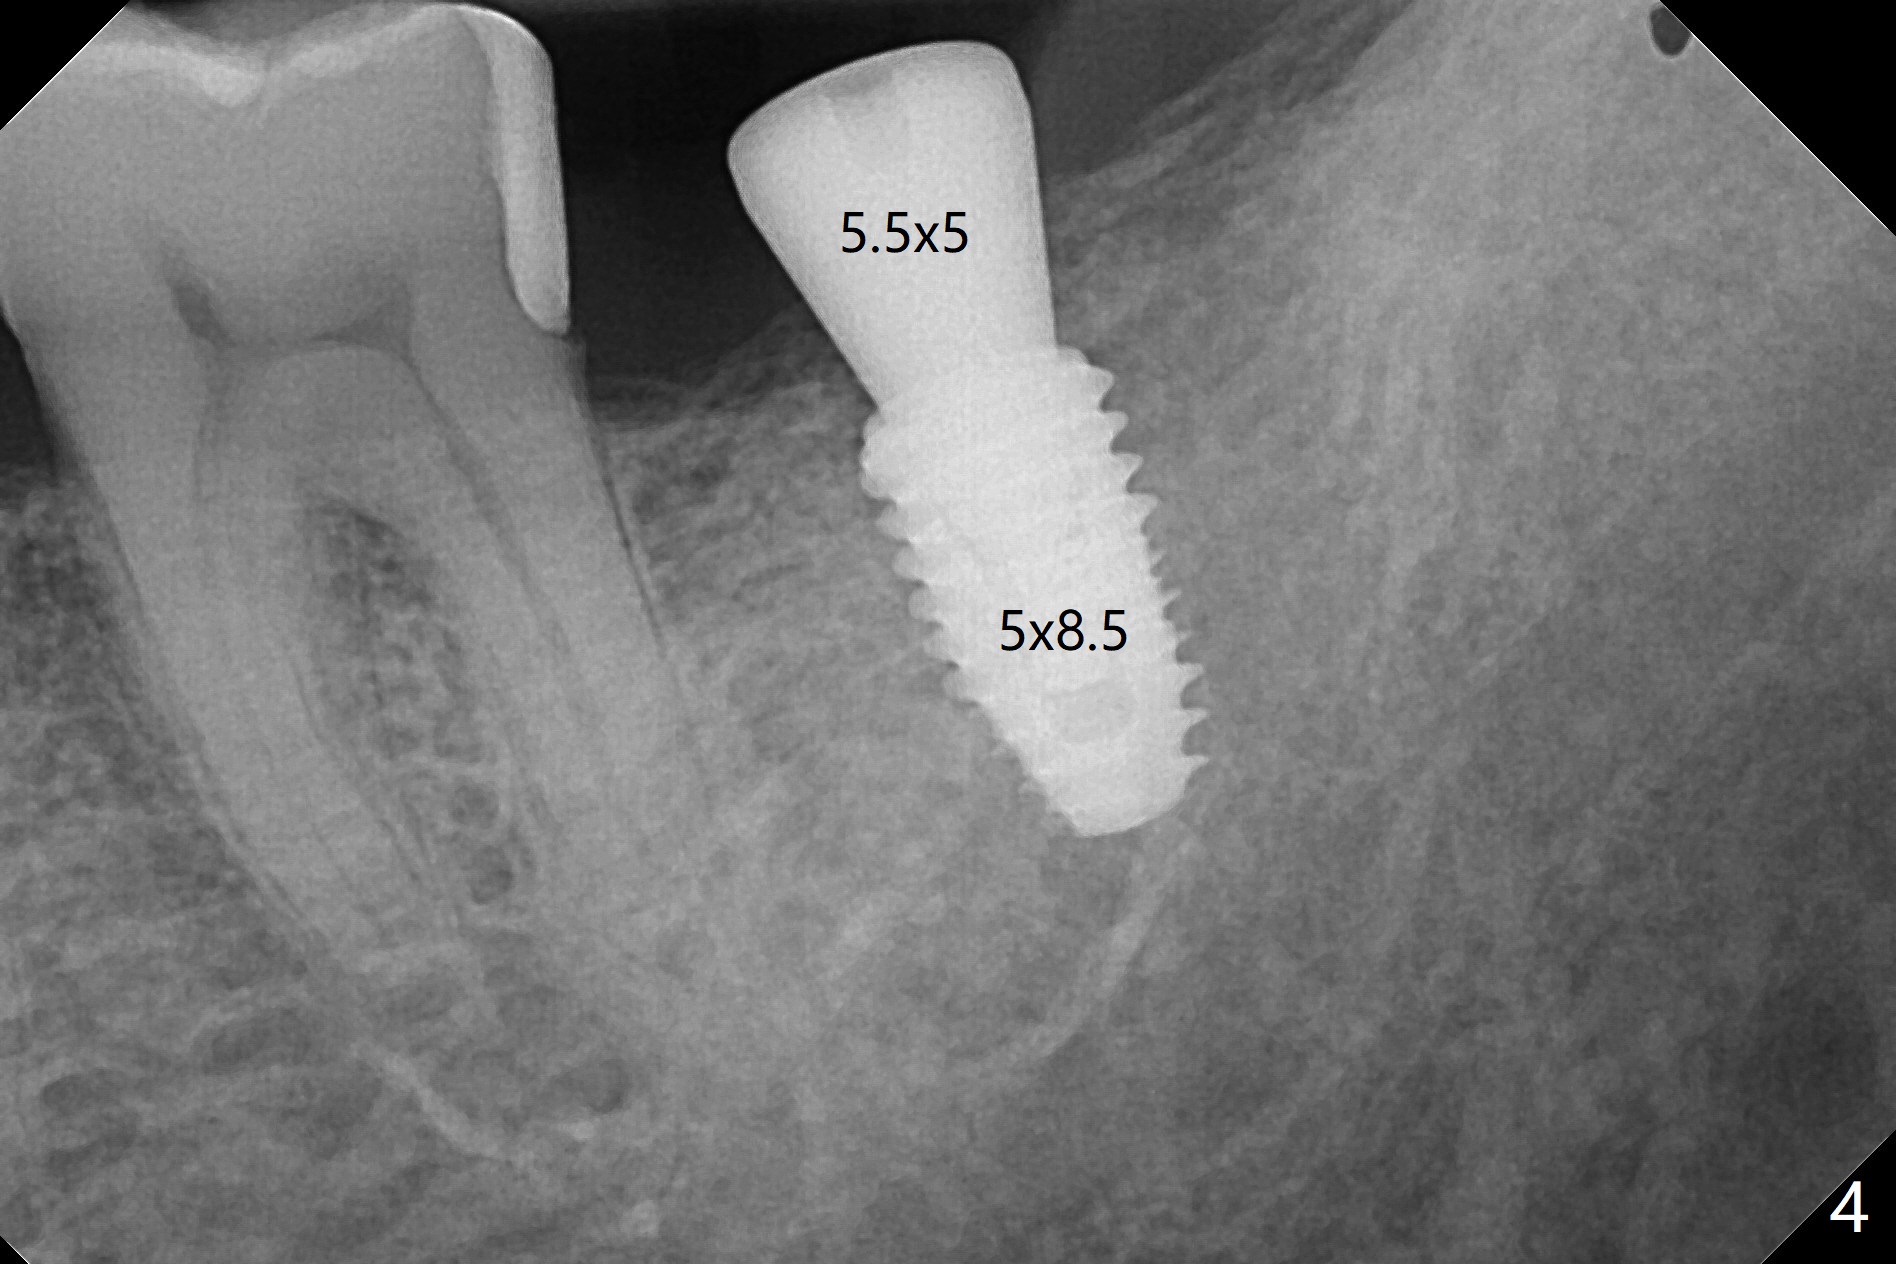

72岁男4.5前左上第二磨牙位置正常(图一),当时左下第二磨牙龋齿严重(图二),后来在别的诊所拔除,最近回来要求左上第一磨牙(图三)和左下第二磨牙种植(图四),由于左上第二磨牙延申(图五),为了左下第二磨牙导板种植,左上第二磨牙近中舌侧牙尖必须磨除不少(图三:*),总之,第二磨牙导板延期种植吃力,下午第二磨牙导板即种就没有这方面困难。